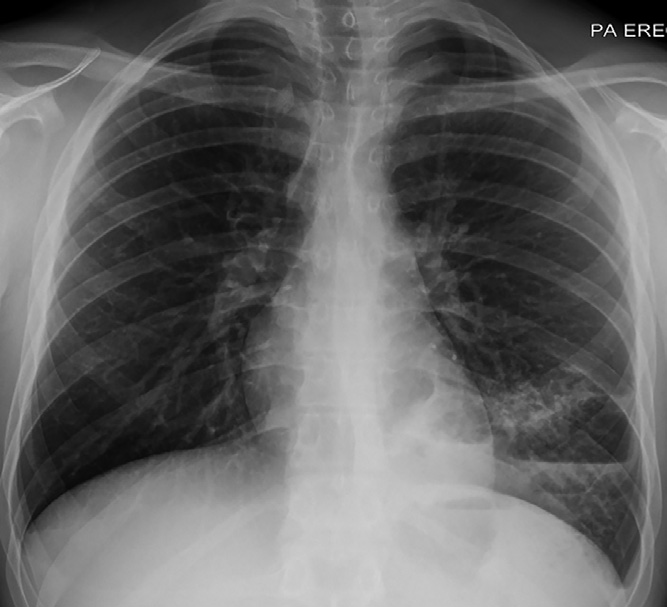

實驗室檢查顯示白細(xì)胞計數(shù)13.6×109/L↑(中性粒細(xì)胞79%;淋巴細(xì)胞12%),C反應(yīng)蛋白96 mg/L↑。胸部X線檢查顯示左肺下葉實變伴氣液平面,考慮與空洞性肺炎相關(guān)(圖1)。增強CT顯示左肺下葉病變,有空氣支氣管征和含氣液平面的空洞及囊狀氣腔。(圖2A–2 C)。人類免疫缺陷病毒抗體檢測、抗中性粒細(xì)胞胞漿抗體、尿肺炎球菌和軍團菌抗原檢測均為陰性,且多組血培養(yǎng)結(jié)果顯示無菌。患者先前未進行IgG及亞類缺陷檢測。

圖1 胸部X線顯示左肺下葉實變伴氣液平面,未發(fā)現(xiàn)明確腫塊。該結(jié)果與空洞性肺炎相關(guān)。